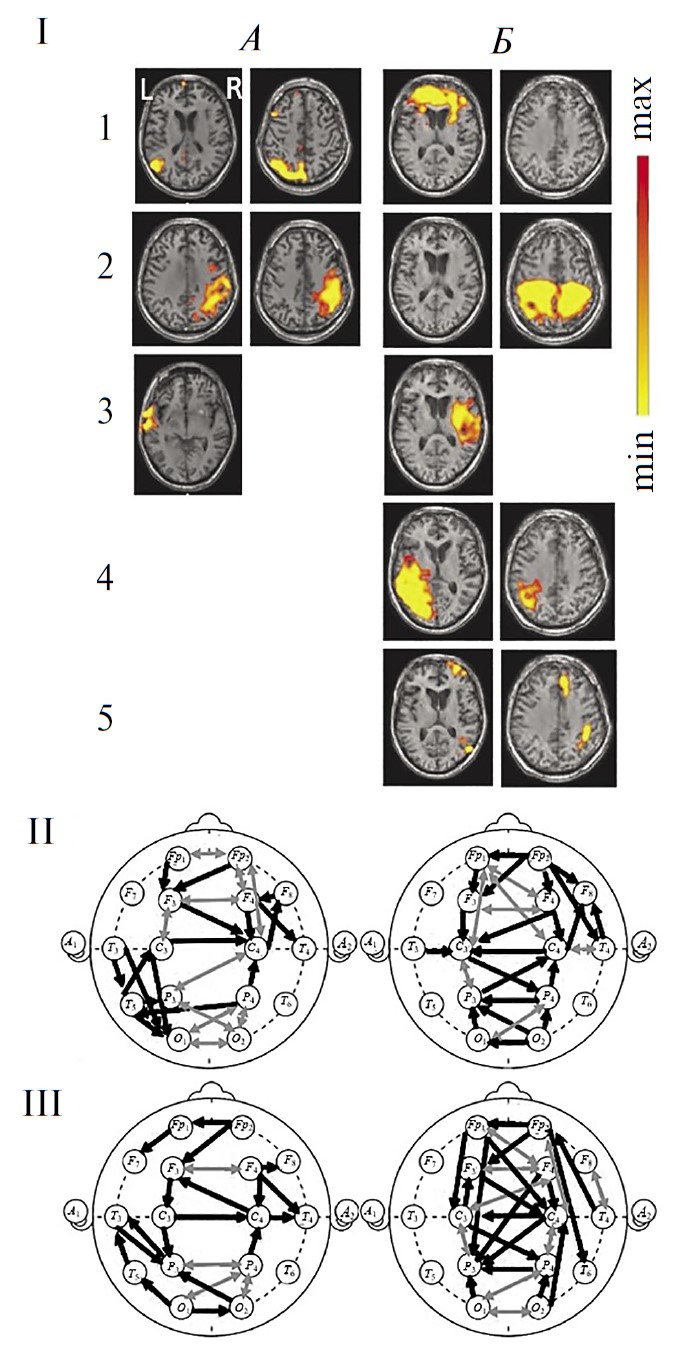

На рис. 2, I представлены изображения RSN фМРТ этого пациента (из числа перечисленных в методике), выявляемых до (рис. 2, I, А) и после рТМС (рис. 2, I, Б) на идентичных аксиальных срезах мозга. В первом исследовании, на фоне вегетативного состояния, удалось верифицировать компоненты лишь 3-х из 6 исследуемых RSN (рис. 2, I, A): DMN, cенсомоторной и слуховой. Однако эти сети резко отличны от нормы асимметричностью и фрагментарностью. В сети DMN доминирует левополушарный каудальный (затылочный) компонент при значительной редукции лобного. Сенсомотороная сеть представлена компонентами в глубинных отделах правого полушария. Слуховая — левосторонней активностью в базальных отделах.

Рис. 2. Динамика сетей покоя функциональной магнитно-резонансной томографии (фМРТ) и коннективности ЭЭГ-диапазона 1–15 Гц в наблюдении 1.

A — исследование 1 (до ритмической транскраниальной магнитной стимуляции (рТМС)), вегетативное состояние; Б — исследование 2 (через 5 дней после курсовой рTMС), состояние, переходное к мутизму с пониманием речи. I — RSN фМРТ: 1 – DMN, 2 – сенсомоторная, 3 – слуховая, 4 – речевая, 5 – лобно-теменная. Шкала справа как на рис. 1. II — коннективность ЭЭГ покоя в непрерывной записи. III — коннективность ЭЭГ покоя в режиме псевдо-ВП. Обозначения линий см. рис. 1.

Во втором исследовании, при переходе к стадии МПР (рис. 2, I, Б), у пациента были выявлены уже 5 RSN фМРТ за счет составляющих лобно-теменной и речевой сетей. Наряду с этим, обращает на себя внимание повышение интенсивности выраженных ранее RSN, подтвержденное количественно (рис. 3), и изменение их пространственной организации. Так, увеличилась билатеральная интенсивность лобного компонента сети DMN, а также моторной коры обоих полушарий в сенсомоторной сети. Выражена распространенная активность височной сети в правой гемисфере. Появились компоненты двух RSN, отсутствовавшие до стимуляции: речевой слева и правой лобно-теменной.

По данным коннективности ЭЭГ покоя (рис. 2, II и III), при первом исследовании и в непрерывных записях ЭЭГ (рис. 2, A, II), и в режиме псевдо-ВП (рис. 2, A, III) отмечается выраженная редукция межполушарных связей, в особенности диагональных. В первую очередь это касается лобной и моторной зон межсетевой интеграции. Кроме того, обеднены внутриполушарные взаимодействия, особенно в передних отделах обоих полушарий, а также затылочно-теменно-височные связи справа. Вместе с тем, представлены не характерные для нормы коннективности ЭЭГ в затылочно-теменно-центральной области левого полушария. Эти особенности ЭЭГ согласуются с асимметричностью компонентов всех выявленных сетей покоя фМРТ и их фрагментарной представленности в пределах полушария.

Во втором исследовании и в непрерывных записях ЭЭГ (рис. 2, Б, II), и в режиме псевдо-ВП (рис. 2, Б, III) наблюдается увеличение числа межполушарных связей ЭЭГ лобно-центральных и затылочно-теменных областей. Эти изменения согласуются с восстановлением билатеральной структуры сетей управляющих функций и сенсомоторной фМРТ покоя (рис. 2, Б, I, 1-2). Кроме того, выявляются двухсторонние внутриполушарные лобно-центральные коннективности ЭЭГ. В режиме псевдо-ВП более отчетливо выражено увеличение числа протяженных внутриполушарных взаимодействий: лобно-теменной слева, а также лобно-височных и затылочно-центральной справа. Перестройки внутриполушарных связей ЭЭГ согласуются появлением компонентов правой лобно-теменной, а также речевой сетей фМРТ покоя.

Таким образом, в наблюдении 1 прослеживается явная тенденция к нормализации пространственной организации связей ЭЭГ и восстановлению ряда локусов межсетевой коннективности — наряду с позитивными изменениями сетей покоя фМРТ.